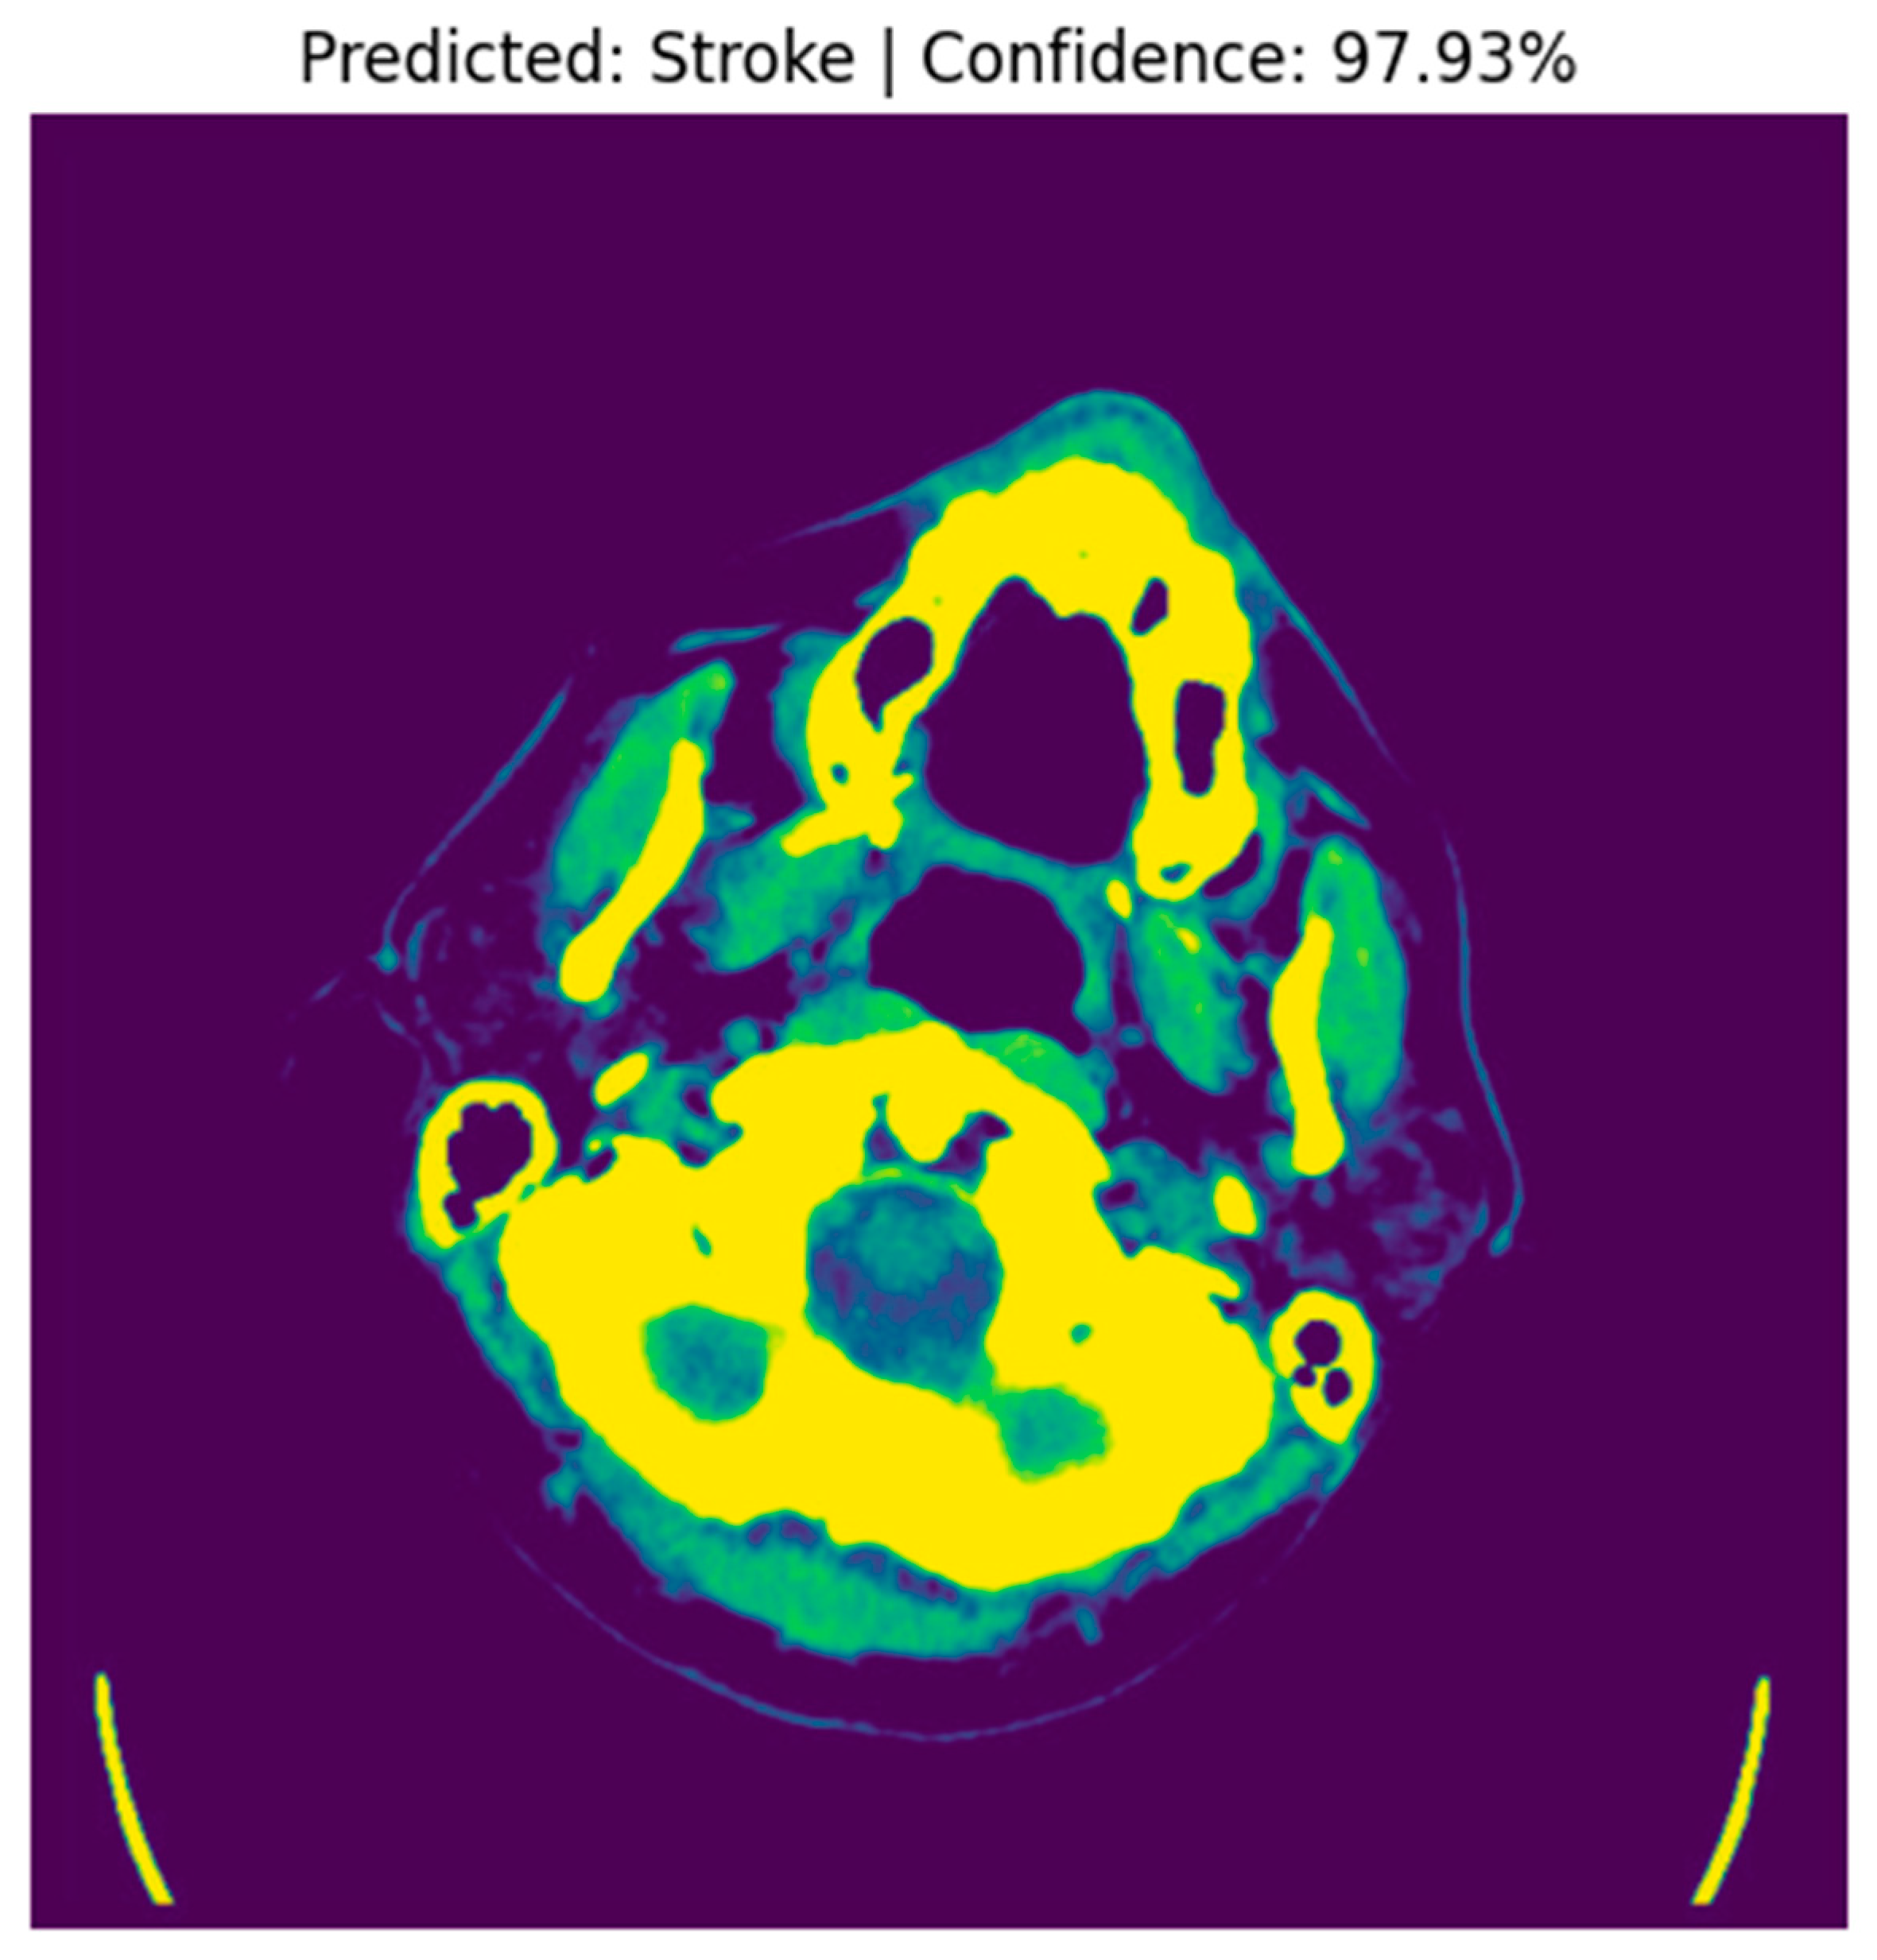

4.4. Stroke Prediction Visualization

4.6.2. Occlusion Sensitivity Mapping

- Bright Yellow/Red Areas (High Occlusion Impact): These regions indicate that occluding them significantly reduces the model’s prediction probability. For example, the hyperdense clot in the left hemisphere (red) is critical for the model’s decision, as its occlusion leads to a substantial drop in the predicted stroke probability. This aligns with clinical expectations, as hyperdense regions are indicative of hemorrhagic strokes.

- Blue/Purple Areas (Low Occlusion Impact): These regions have minimal influence on the model’s prediction. For instance, the background or non-brain tissue areas (blue) do not affect the stroke classification when occluded, confirming that the model focuses on anatomically relevant regions [24].